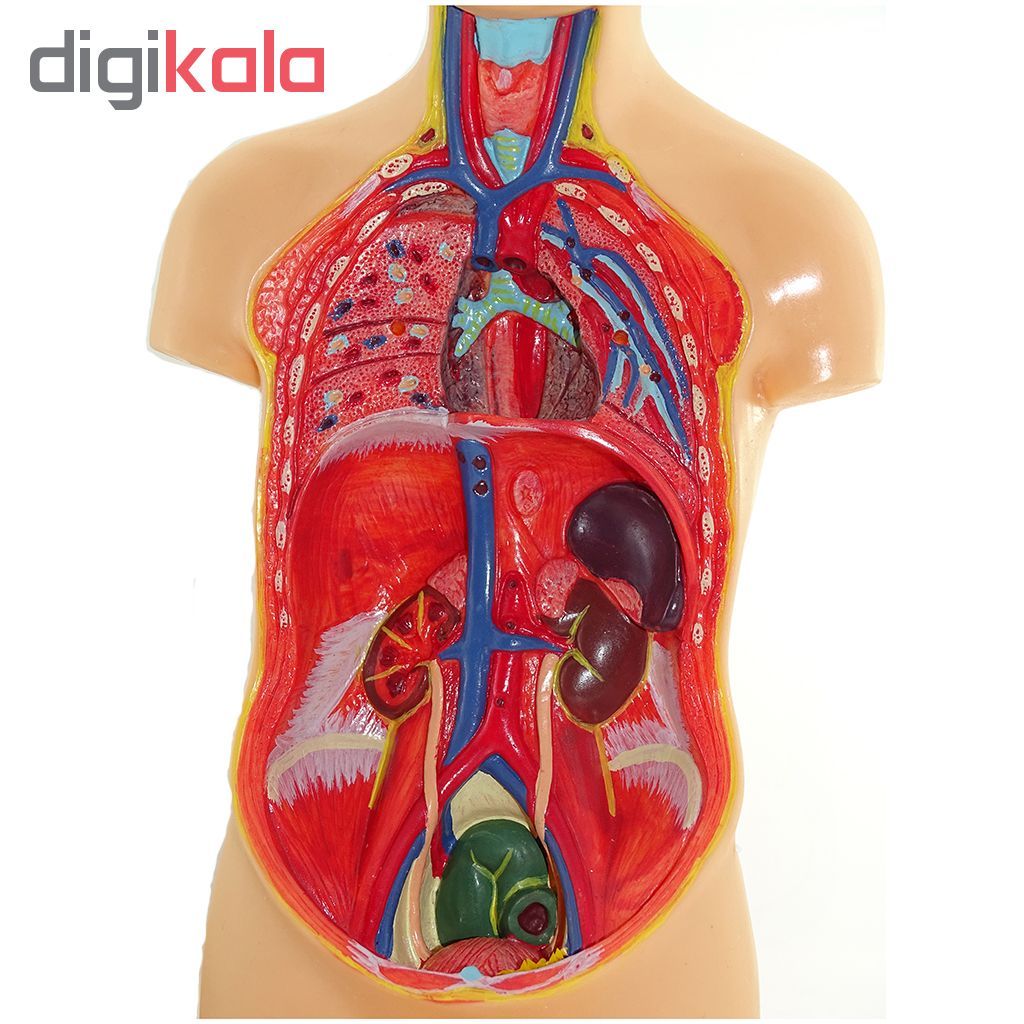

عکس داخل شکم انسان. در این همان طور که مشخص است شکم حالت بیضی شکل پیداکرده و این بیضی که کناره های شکم کشیده شده است. تعداد سلول های بدن انسان حدود ۳۷ ۲ تریلیون تخمین زده شده اند. Abdomen که در زبان عامه به غلط به آن دل نیز می گویند در آناتومی به قسمتی از تنه گفته می شود که مابین دیافراگم از بالا و سطح فوقانی لگن خاصره از پایین قرار دارد. ربات دیدنی ربات انساننمای چینی به صورت یک دختر جوان ساخته شده و جیا جیا نامگذاری شده است این ربات طوری برنامهریزی شده که میتواند صحبت کند و احساسات خود را از طریق تغییرات در چهره حالات.

شکل دوم شکم مادری را نشان می دهد که جنین دختر دارد. وحشت مادر از عکس سونوگرافی جنین داخل شکمش عکس. تصاویر جالب از داخل مغز و نخاع انسان آخرین نیوز. بدن انسان کل ساختار انسان است که سر گردن تنه سینه و شکم دو بازو و دست ها و دو ساق پا و پاها را شامل می شود.

به گفته مایک جنس استخوان دنبالچه آخرین بقایای دم انسان است و جالب تر اینکه تمام پستانداران دنیا در شکم مادر دم دارند و فقط انسان است که قبل از تولد ان را از دست می دهد.